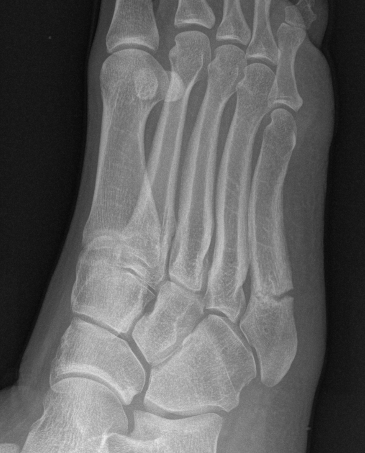

Xray

Zone 2 fractures

Union of zone 2 fracture with nonoperative care